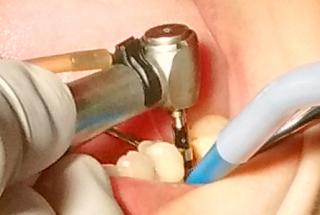

Clinical cases

MPI closely monitors clinical cases in the market to ensure their correct functioning and successful outcome.